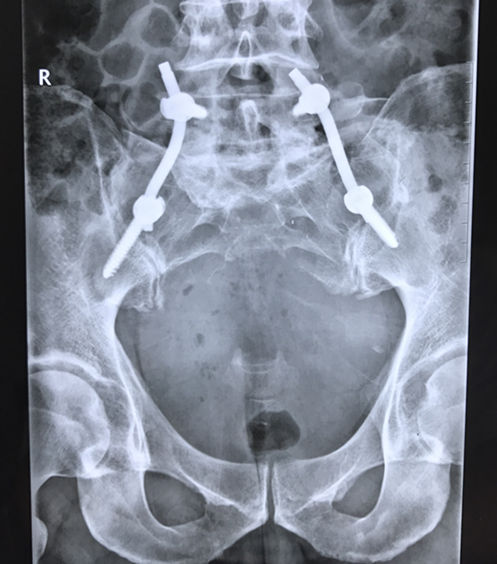

经过充分的术前准备,手术正式开始。在麻醉科的支持下,介入科熊壮主任在患者腹主动脉放置球囊,以防术中大出血。由关节与骨肿瘤外科胡勇主任主刀,在胡博医师等的配合下,后路完整切除直径约15cm的骶骨巨大肿瘤,并进行腰骶部重建。术后患者生命体征平稳,双下肢运动感觉正常,并能保留70%大小便功能。

据胡勇主任介绍,巨大骶骨肿瘤切除术,是我省罕见且难度巨大的外科手术。此次患者的手术时间仅为3个小时,出血量仅有800ml,术后患者的生命体征平稳,双下肢运动感觉正常,保留大部分大小便功能,取得了良好的疗效。本例手术的成功不仅是对术者技术的考验,也反映了医院多学科的合作水平。